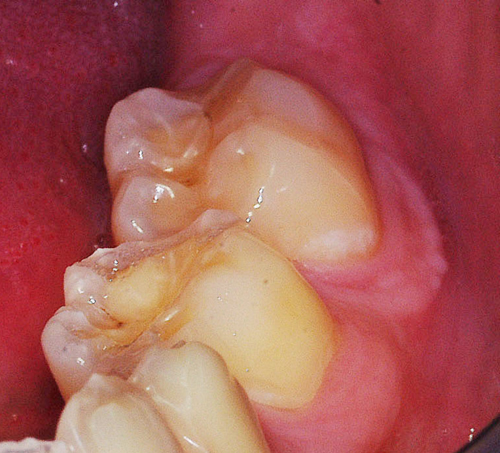

REHABILITACION ORAL MEDIANTE CORONAS DE PORCELANA DE ALTA DENSIDAD Protocolo D.A.T.O. CASO CLINICO: Paciente 24 años, bruxómano, atresia maxilar, referido por ortodoncista para realizar rehabilitación oclusal . Se observa a la inspección la presencia de una hipoplasia adamantina en todos los dientes anteriores, carencia de Guía Anterior , evidentes signos de Facetas Parafuncionales de Desgaste en los posteriores, y una marcada convergencia de los ejes dentarios ápico oclusal, tanto en el maxilar superior como en el inferior, siendo el superior el mas difícil de resolver dado que la inclinación de la Curva de Wilson es inversa a lo que presenta el enfermo. Radiograficamente sin patologías presentes. No presenta movilidades dentarias ni síntomas articulares en las ATM. Debido a la excesiva contractura de su musculatura, se realiza la relajación obviando el uso corriente de las Laminillas de Long, reemplazando el método por un Jig de Lucia el que se deja en boca desde la noche anterior a la cita, advirtiendo al paciente que no debe quitarlo en ningún momento , ya que de hacerlo se repetirían los engramas musculares anómalos que el enfermo presenta. En esas condiciones se toman registros intermaxilares mediante silicona de registros, y se registra el maxilar superior respecto del plano de Frankfort mediante arco facial estático. Se llevan a cabo los encerados correspondientes y se construye en base a ellos el primer juego de provisionales, los que no son cementados debido al perfecto anclaje que presenta. Transcurridos seis meses del uso de provisionales , durante los cuales se ha observado la Oclusión en Relación Céntrica (ORC) inalterable, la ausencia de desgastes patológicos (en las provisorias) y la ausencia de síntomas articulares y musculares, deducimos que el paciente se mantiene en una orto función adecuada, por lo cual comenzamos su rehabilitación definitiva construyendo su Guía Anterior ( determinante primario de la oclusión) en porcelana sobre porcelana de alta densidad.. Observamos los espacios correspondientes en los sectores posteriores y las Disclusiones de los mismos. Los tallados ha sido realizados mediante el concepto de Tallados Gnatológicos, recreados por el Prof. Alvarez Cantoni bajo la denominación de “Preparaciones Racionales”( PREPARACIONES RACIONALES EN PRÓTESIS PARCIAL FIJA. Ed. Hacheace) probando finalmente el trabajo luego de varios días de cementado provisional, y observando la adaptación periférica del borde cavo superficial , su aspecto estético y el importante factor disclusivo : CURVA DE WILSON. y verificando la eficacia lograda mediante una Oclusión Mutuamente Compartida, en la observación de una Disclusión derecha en el Lado de Trabajo y no Trabajo de una disclusión izquierda como así también en la disclusión propulsiva Utilizamos papel de articular de ocho(8) micras para verificar la eficacia de las disclusiones. y de los puntos interoclusales de contacto ANTES DESPUES

Facetas estas donde puede observarse el típico fenómeno de “DESGASTE EN OLLA”, constituido por el facetamiento doblemente profundo de las Cúspides Estampadoras respecto de las Cúspides de Corte.